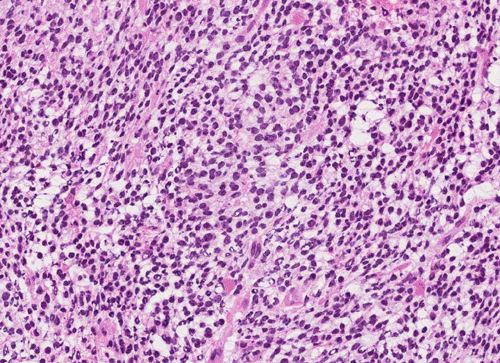

Pathology of the Case: The tumor is composed of neoplastic small blue cells on the cytologic preparation (Pancel C and D) with only minimal amount of cytoplasm. On frozen section (Panel E and F), the tumor cells are packed in solid sheets without specific pattern of arrangement. On permanent sections, the tumor again is composed of solid sheets of small blue cell tumors with rather monotonous nuclei (Panel G and H). In some areas, there is some small neuropil islands (Panel I). No distinct perivascular coronary arrangement is noted.  (Panel J). There is a moderate labeling index on Ki67 (Panel K). The tumor cells are strongly positive for neurofilament proteins (Panel L). Some large stellate, cells positive for glial fibrillary acidic protein (GFAP) are also present and these cells may represent reactive astrocytes (Panel M).

In essence, PPTID is composed of diffuse sheets or large lobules of  uniform cells with mild to moderate nuclear atypia and low to moderate levels of mitotic activity.  Differentiation of grade II and III tumors can be made based upon a combination of mitotic activity levels and neurofilament protein immunoreactivity. Rare mixed tumors exhibiting characteristic elements of both pineocytoma and pineoblastoma have also been classified as PPTID, albeit somewhat controversially. The tumor classification of PPTID originated in 1993 with the work of Schild, et al. reviewing data on 30 patients with pineal parenchymal tumors diagnosed between 1939 and 1991. Of the 30 pineal parenchymal tumors, four were sub-classified as PPTID by Schild and his colleagues 9.

PPTID has a histopathologic picture of a small blue cell tumor. However, the degree of pleomorphism is not as high as pineoblastoma or medulloblastoma. Particularly for the one with better differentiation, the cells would have overall features suggestive of lymphocytes. This would further suggest germinomas as they are associated with a substantial amount of lymphocytes. Search for large germinoma cells would be the diagnostic clue to distinguish these two categories. Histological distinction of PPTID with teratomas, yolk sac tumors, embryonal cell carcinomas, and choriocarcioma components in germ cell tumors is relatively straightly forward. The table below provides comparison of different types of pineal parenchymal tumors.